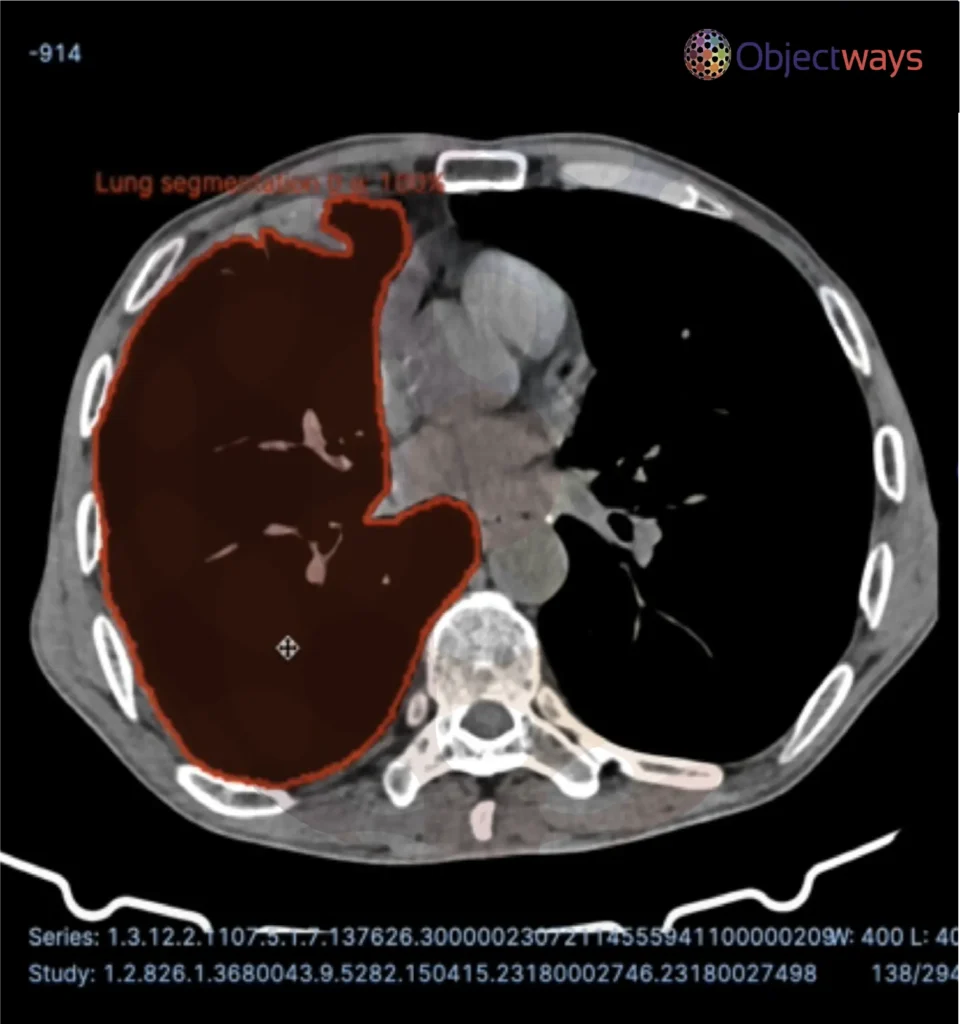

Next, let’s walk through how these data types can be used in real-world applications and why high-quality data is the DNA of AI. A popular application of AI in healthcare involves AI models being trained on meticulously labeled medical scans, such as X-rays or MRIs, to detect diseases like cancer or identify abnormalities. The precision of these labels directly impacts diagnostic accuracy. High-quality data can indirectly improve patient outcomes.

Using AI to detect brain tumors.